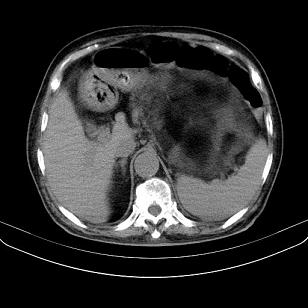

标题: CT21671:男,88岁,左上腹包块 [打印本页]

标题: CT21671:男,88岁,左上腹包块

患者因咳嗽而住院,自觉右上腹包块,无其他不适。

支持;后腹膜脂肪肉瘤诊断。

另肠腔扩张及液平,肠梗阻?

考虑腹膜后脂肪肉瘤可能性大。 畸胎瘤不除外。